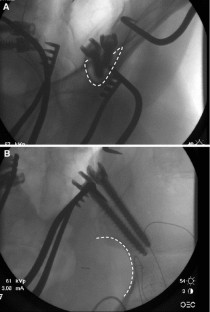

Sacropelvic fixation should be considered in any patient with a long construct ending in the sacrum, those patients with associated risk factors for loss of distal fixation or high risk for pseudarthrosis at L5–S1, and those undergoing three column osteotomies or vertebral body resections in the low lumbar spine. Current pelvic fixation techniques with iliac screws, multiple screw/rod constructs, and S2-alar-iliac screws are all viable techniques for achieving pelvic fixation.

There is growing evidence that pelvic fixation may become the standard for obtaining long fusions in adult scoliosis. Although technically challenging, in selected cases the use of four pelvic screws and/or four rods across the lumbosacral pelvis can help address pseudarthroses, implant breakage, and screw pullout secondary to osteoporosis. Ultimately, indications and techniques should be individualized to the patient and based on surgeon preference and experience.